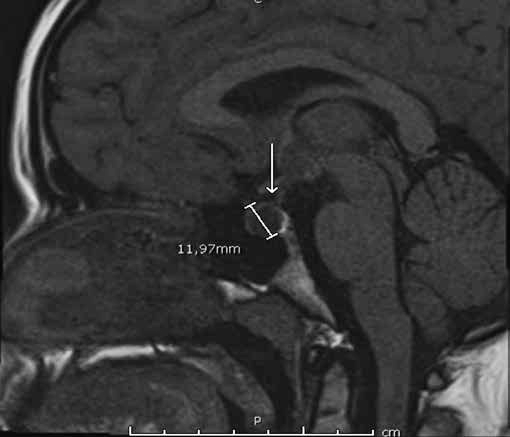

Figura 1b. RM de si a lla turca contrastada con gadolinio. Corte sagital en T2. Cortes 2.5 mm.

Se informa a continuación los estudios de imagen. Ecografía ginecológica (estudio previo indicado por ginecología): útero de forma y tamaño normal que mide 52 x 21 x 29 mm, endometrio de 5 mm, ovario derecho 25 x 18 mm, ovario izquierdo 28 x 17 mm. RM de silla turca: glándula hipofisaria aumentada de tamaño que mide 1,0 cm de altura, 1,9 cm de ancho, 1,2 cm anteroposterior, imagen de comportamiento quístico en las diferentes secuencias con realce homogéneo del parénquima glandular que rodea la lesión quística y se mantiene hipointensa en T1 (Figura 1a), tallo hipofisario en la línea media, quiasma óptico y estructuras vasculares sin compresión. En T2 se aprecia parénquima glandular hiperintenso (Figura 1b). Campo visual sin alteraciones.